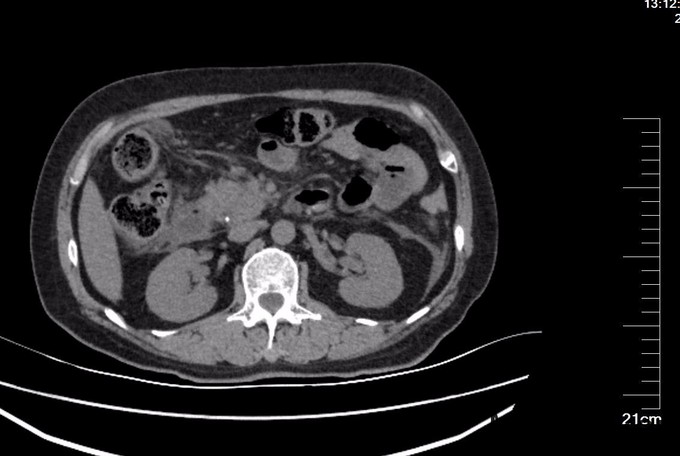

查体: 腹平坦,未见胃肠型及蠕动波,腹软,右上腹压痛明显,伴反跳痛,无肌紧张,肝脾肋下未扪及肿大,无移动性浊音,双肾区无叩痛,肠鸣音存在。 辅查:超声检查: 胆囊大小约6.1x2.4cm,壁厚约0.3cm,囊内见多个强回声团,较大者直径约0.9cm,声影(+),移动(+)。 胰腺轮廓模糊,胰腺头、体厚度分别为2.4cm、2.6cm,回声粗糙,主胰管直径约0.1cm。胰尾部受肠气干扰显示不清。 腹腔未见明显积液影像。 CT提示:肝内外胆管未见明显扩张,胆囊壁稍厚,内见结节状高密度影,直径约1.9cm。胆总管下段细点状高密度影,大小约0.2cm,胰腺边界模糊,周围多发条状絮状渗出影,双肾前筋膜增厚,十二指肠管壁模糊。血淀粉酶(AMY)、血脂肪酶(LPS )及尿淀粉酶(Amy-U)明显增高(见图里化验报告)。

诊断: 胆囊结石 胆总管结石 胆源性胰腺炎 治疗:胃肠减压,抗炎,补液,抑酶,抑酸治疗,急诊内镜至十二指肠,见十二指肠乳头肿胀,选择性胆管插管顺利,造影见胆总管直径12mm,末段可见数处充盈缺损,最大大小约6mm,行乳头肌切开(EPT),以12mm球囊扩张乳头(1ATM,40s)后,取石球囊取出黄色结石1枚及少许泥沙样结石,球囊及盐水清理胆道,再次造影见胆总管内无充盈缺损,留置鼻胆引流管,选择性胰管插管顺利,留置5Fr5cm胰管塑料支架一枚。次日,患者血淀粉酶恢复正常,血脂肪酶降至156U/L,腹痛明显缓解。EPT第二日,全麻下腹腔镜胆囊切除术(LC),手术顺利,术中发现胰腺无坏死,未处理胰腺,LC术后2天再次经EPT留置的ENBD管造影,未发现胆总管结石,复查血淀粉酶及脂肪酶,均恢复正常,拔管出院。